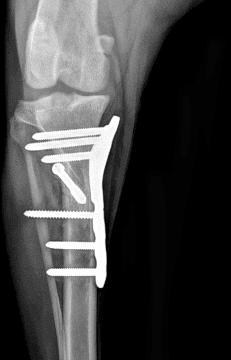

정형외과 전공의 수의사가 직접 수술합니다.

12정교한 정형외과 도구를 사용하여 신속 정확한 정형외과 수술이 가능

13수술 중 골절 상태 혹은 이식물 적용 후 상태 등 육안으로 명확히 확인하기 힘든 상태를 X-ray 확인하여 정확한 수술 결과를 만들어 내는 것이 가능